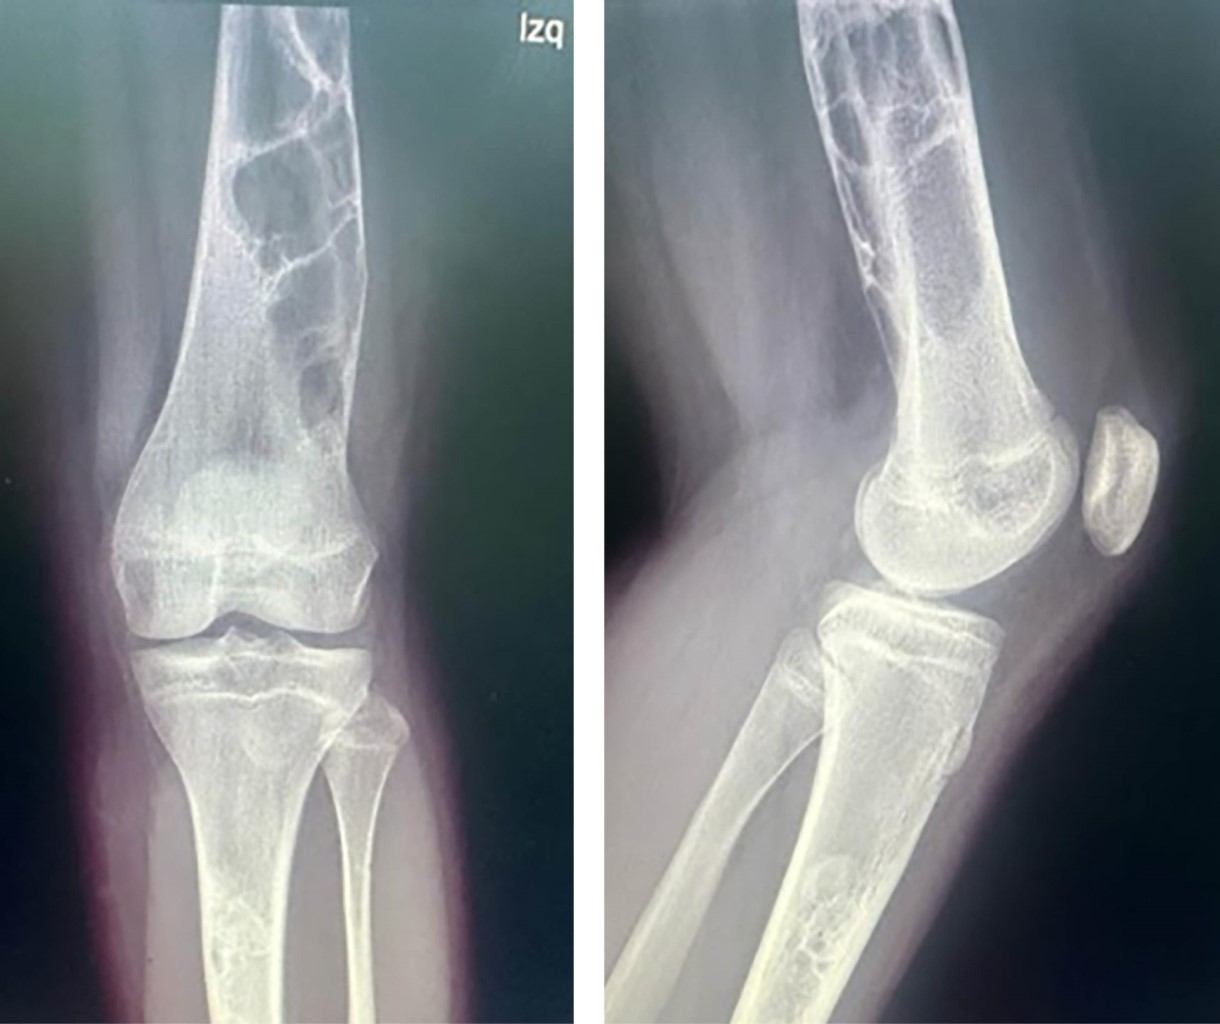

Paciente adolescente femenina de 12 años es evaluada en compañía de su madre, derivada por gonalgia izquierda en estudio de un año de evolución y tumor de fémur distal y tibia proximal izquierda, que se evidencia en radiografía anteroposterior (AP) y lateral de rodilla izquierda (Figura 1) y en radiografía AP y lateral de fémur distal izquierdo (Figura 2). Al examen físico presenta claudicación a la marcha y rango de movilidad de rodilla izquierda disminuido con dolor a la flexión > 90°. Se realizó resonancia magnética nuclear con contraste (Figura 3) con el hallazgo de una lesión hipercaptante, hipointensa en T1, hiperintensa en T2, además de lesión cortical a nivel de ambos fémures distales. Se complementa estudios con exámenes endocrinos con resultados dentro de límites normales y radiografías de huesos largos descartando algún otro foco de lesión.

Figura 2